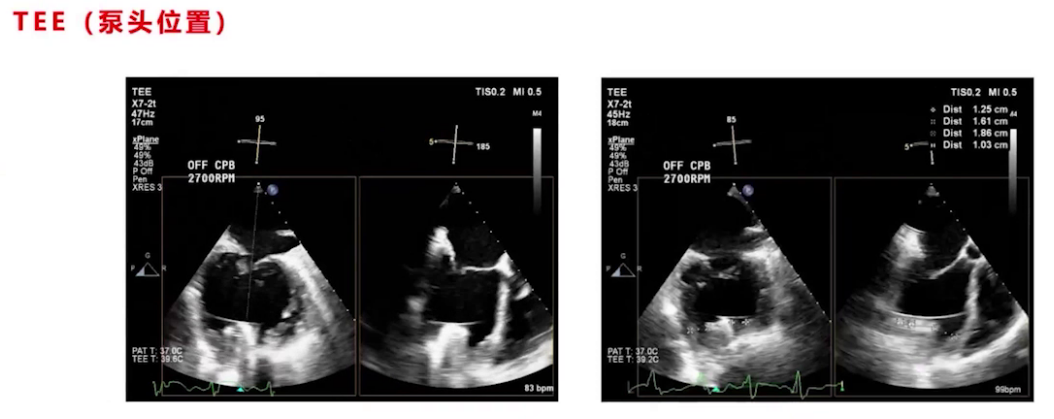

停机前TEE评估无气体,泵头及流出导管位置良好,调节过程中监测心室大小、室间隔形态及心功能,最终转速设为2700转,左室大小从术前71/72降至67左右,右心功能较术前稍有改善。